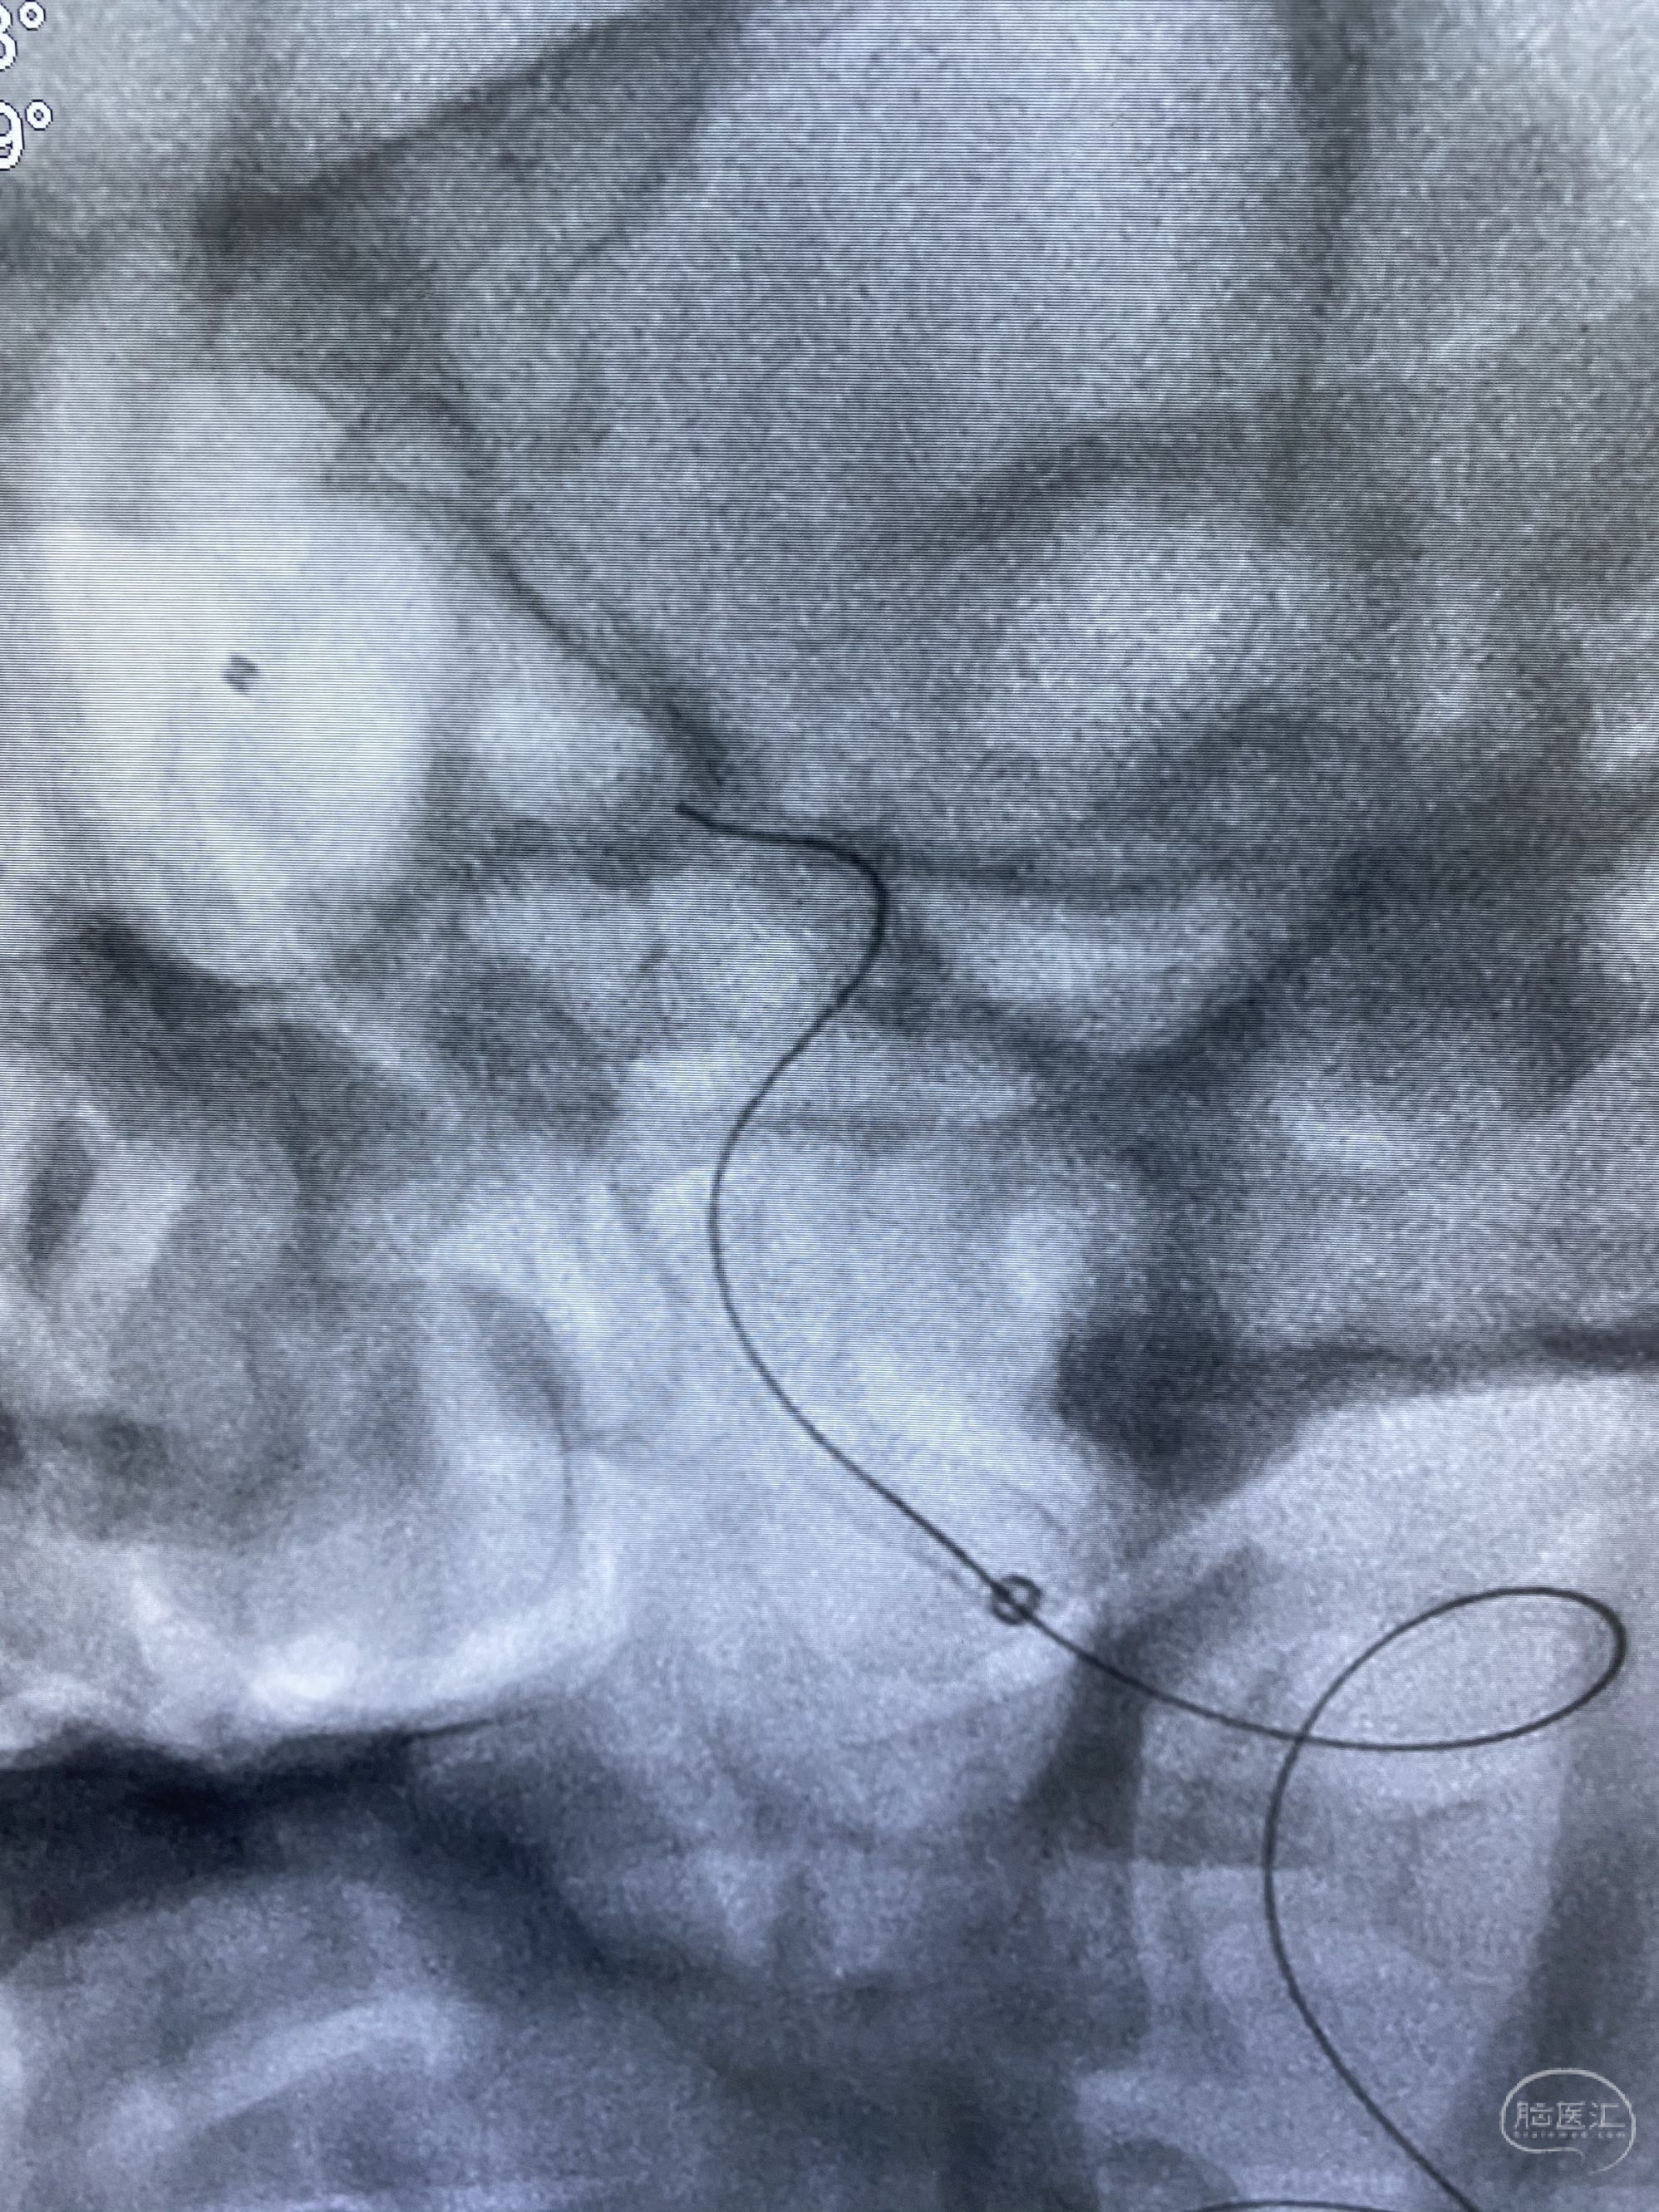

今日手术,TJG,M62Y,一期左侧颈动脉狭窄支架植入,二期椎动脉V4段多发夹层动脉瘤伴狭窄,常规支架辅助栓塞方法复杂又危险,血流导向装置植入快捷又安全。南阳市中心医院神经内科脑血管病介入团队pipeline flexFD植入两人导师资格。

椎动脉颅内段多发夹层动脉瘤伴载瘤动脉狭窄pipeline flex植入

今日手术,TJG,M62Y,一期左侧颈动脉狭窄支架植入,二期椎动脉V4段多发夹层动脉瘤伴狭窄,常规支架辅助栓塞方法复杂又危险,血流导向装置植入快捷又安全。南阳市中心医院神经内科脑血管病介入团队pipeline flexFD植入两人导师资格。